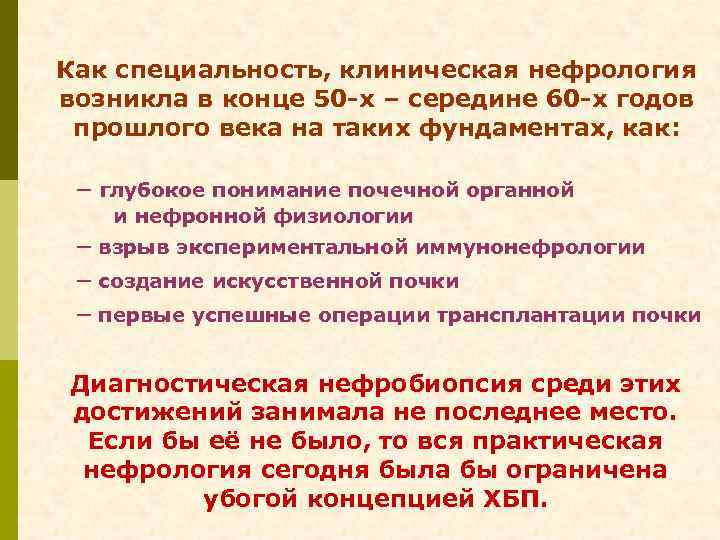

Как специальность, клиническая нефрология возникла в конце 50 -х – середине 60 -х годов прошлого века на таких фундаментах, как: – глубокое понимание почечной органной и нефронной физиологии – взрыв экспериментальной иммунонефрологии – создание искусственной почки – первые успешные операции трансплантации почки Диагностическая нефробиопсия среди этих достижений занимала не последнее место. Если бы её не было, то вся практическая нефрология сегодня была бы ограничена убогой концепцией ХБП.